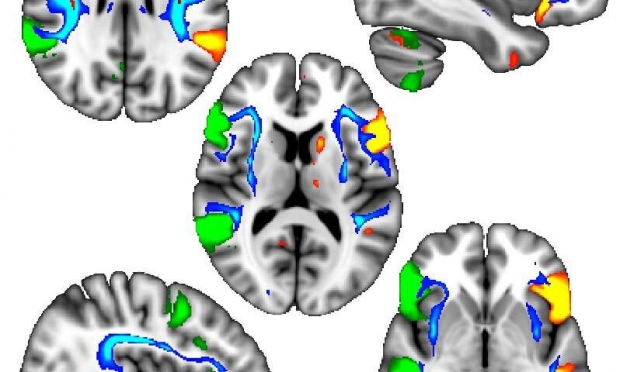

특히 이번 연구에서는 왼손잡이와 관계한 유전자 영역 4개 중 3개가 태아 시기 두뇌 발달과 구조(패턴화)에 관여하는 단백질과 연관돼 있었다. 이 단백질은 미세소관의 발달에 관여하는 데 세포 내에 존재하는 이 기관은 세포 골격의 유지와 세포 이동, 세포 내 물질 이동 등에 필요하다.

이에 대해 영상 분석을 수행한 제1저자 아키라 위베르그 박사는 “우리는 왼손잡이 참가자들의 경우 뇌 좌반구와 우반구의 언어 관련 영역이 더 조화롭게 상호 작용하는 것을 발견했다. 이는 언어적 작업을 수행할 때 왼손잡이들이 유리할 수도 있다는 흥미로운 가능성을 제기하지만, 이런 차이는 매우 많은 사람에 관한 평균으로 보이는 것일 뿐 모든 왼손잡이가 비슷하지 않다는 점을 기억해야 한다”고 설명했다.